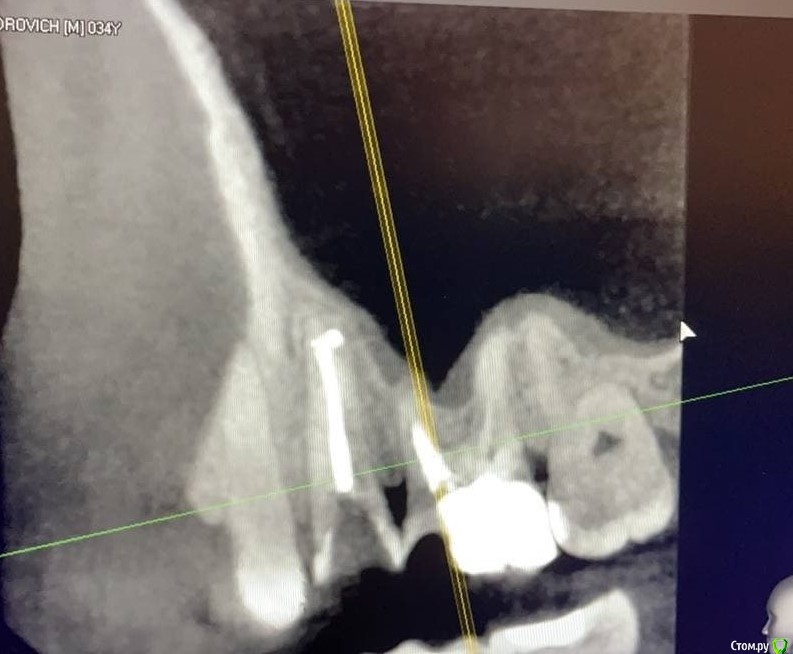

1586Doc Опубликовано 8 февраля, 2020 Поделиться Опубликовано 8 февраля, 2020 5 месяцев назад обратилась пациентка с симптоматикой периодонтита. Оценили, попробовали. Пломбировка вертикалка. 5 месяцев и контроль, боли нет, подвижности тоже. 2 Ссылка на комментарий

1586Doc Опубликовано 10 февраля, 2020 Автор Поделиться Опубликовано 10 февраля, 2020 (изменено) А где контроль на сегодня? При таком качестве снимков оценить будет тяжело.первые 2 фото снимки 9 месяц назад, до ревизии Изменено 10 февраля, 2020 пользователем 1586Doc Ссылка на комментарий

1586Doc Опубликовано 10 февраля, 2020 Автор Поделиться Опубликовано 10 февраля, 2020 (изменено) Имхо пока не вижу успеха. ((ну если еще с 46 я могу понять, 45 явно деструкция в разы меньше. 100% месяца через 3-4 назначу клкт Изменено 10 февраля, 2020 пользователем 1586Doc Ссылка на комментарий